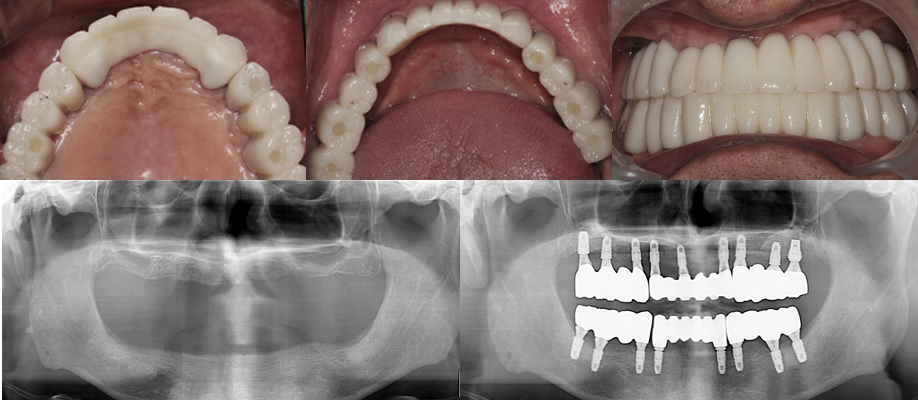

최소 식립으로

전체적인 치아 생성,

기능성과 심미성 회복

환자 성함 : 강** / 65세

2021.07.01 초진 사진

2022.11.30 치료 완료 사진

살릴 수 있는 치아는 최대한 살린 후

최소식립으로

전체적인 기능성과 심미성 회복